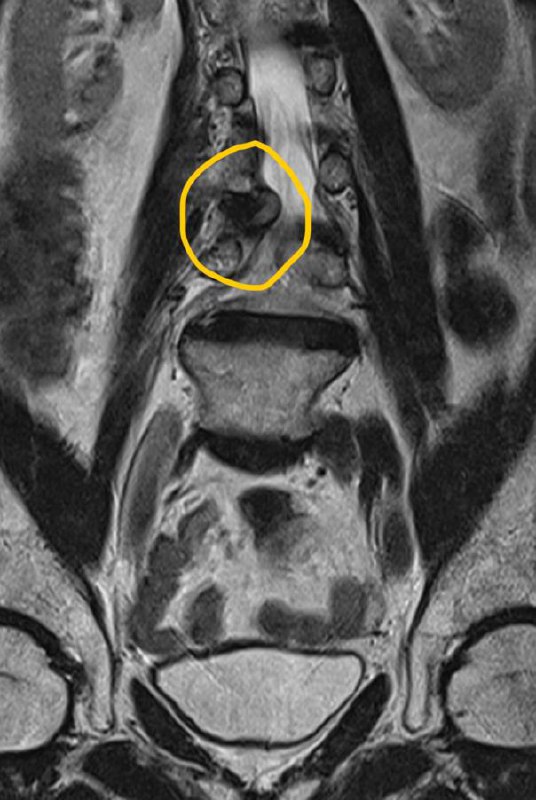

По опыту скажу: когда видишь вот такого, худющего пациента, с таким черным (особенно на Т1, хотя и на Т2, как правило, тоже) костным мозгом, да ещё и со спондилодисцитом, можно не сомневаться, что перед тобой - ВИЧ-инфицированный, и CD4-клеток у него уж точно меньше 150.